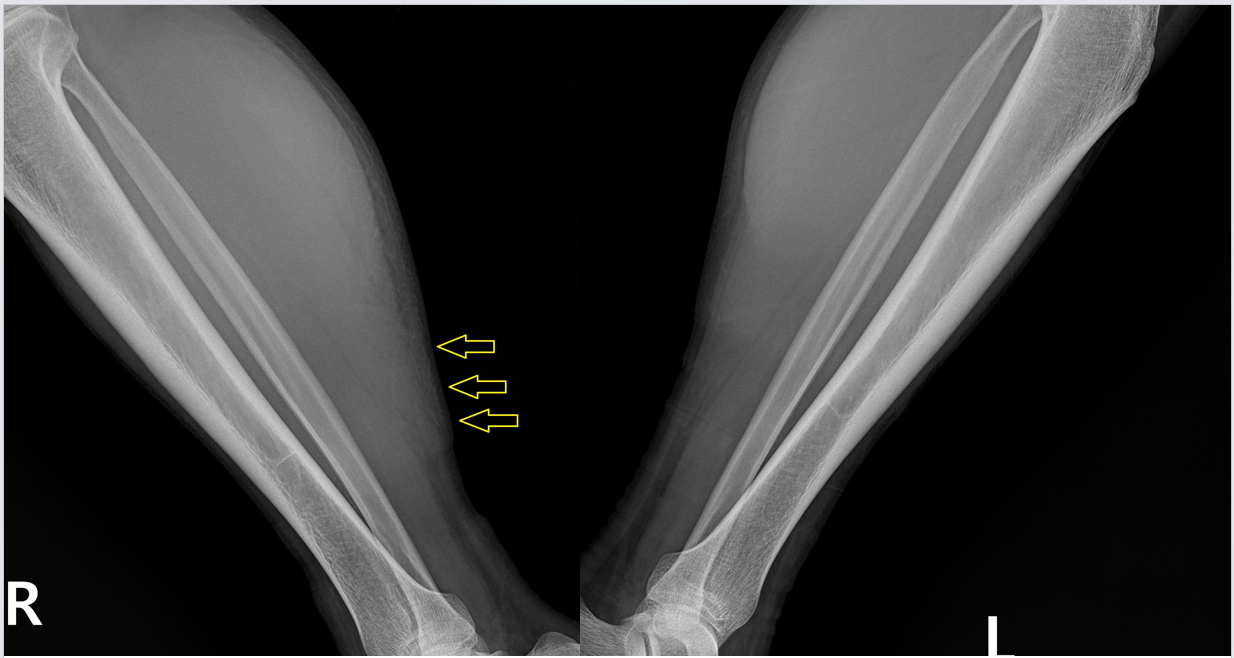

초음파 검사를 하니 근육 파열을 더 자세히 확인할 수 있습니다. 근육은 각각 근막으로 둘러쌓여 있고 이게 근육과 근육을 얇게 구분해주고 있는데요, 근육이 찢어지면 보통 이 근막이 벌어지게 됩니다. 이 환자분도 근막이 벌어지는 근육파열 양상을 보이고 있습니다

다시 촬영한 초음파 검사는

근육 파열이 훨씬 심해지고 근막이 다 벌어지면서 피가 고여있는 모습을 보이고 있습니다.